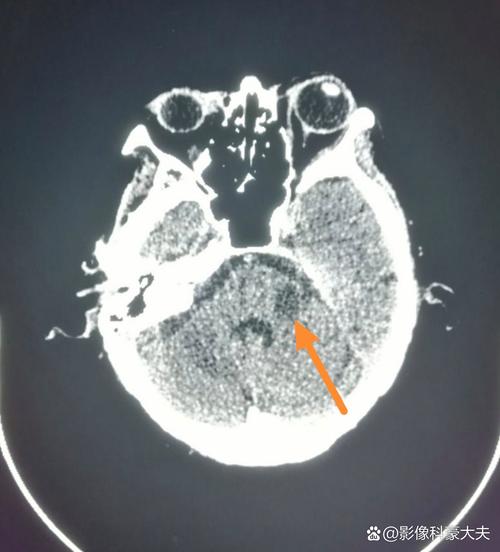

- CT表现: 因为脑组织的密度没有发生显著改变,所以高分辨率的CT在此时往往显示完全正常,无法与健康的脑组织区分开来,医生称之为“阴性CT”或“CT早期征象阴性”。

- 豆状核征: 在基底节区,由于对缺血更敏感,正常情况下密度较高的豆状核可能会变得模糊,与周围密度较低的苍白球界限不清。

- 大脑中动脉高密度征: 少数情况下,可以在CT上看到堵塞的大动脉(如大脑中动脉)因内有血栓而密度增高,但这并非特异性表现。

到了发病24-48小时后,CT上的低密度灶会变得非常明显和清晰,此时诊断脑梗死就非常容易了。